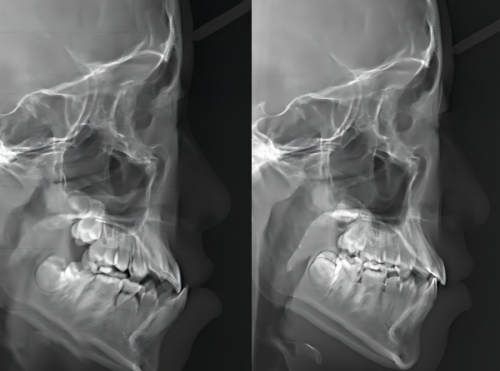

(三)设备精良,精细诊疗

北京有来口腔医院配备数字化口腔CT、进口种植机、隐形矫正设计系统等设备:口腔CT可精细测量牙槽骨密度和神经管位置,为种植牙提供三维规划;隐形矫正系统能模拟治疗过程,让患者提前看到矫正成效,提升治疗信心。